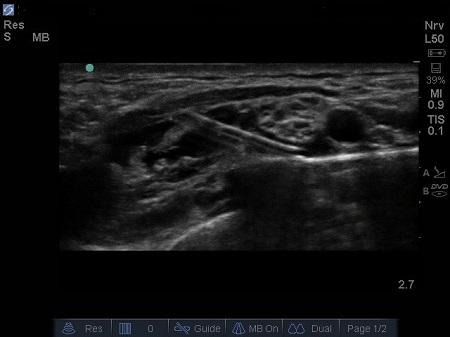

- A linear hyperechoic structure immediately deep and lateral to the A is the first rib with its bony shadow. However, in small children the cortical layer of ribs is thin enough that you can see both layers of the rib cortex and visualise lower down another bright line: the parietal and visceral pleura interface. See Fig. 3.

- Identify also another linear hyperechoic structure, which will be the pleura. Note the air artefact (the “comet tail” sign) and the pleura sliding movement during respiration.

Fig. 3. Sonoanatomy of infant supraclavicular region. A – Subclavian artery. B – brachial plexus, P – pleura, R – first rib, V – subclavian vein